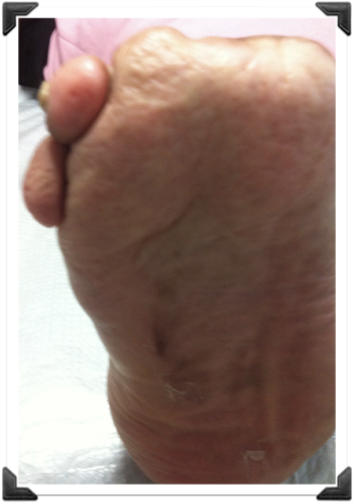

Sindrome Neuroisquemico

Nunca Cirugia

Hasta Tener Flujo

Neuropatía de Charcot

Pre y Post op

Dr. Luis Villanueva

Pie de Charcot

Dr. Luis Villanueva

Úlcera Neuropática 4to MT

Simple Osteotomía Percutánea

SRIS

Dr. Luis Villanueva